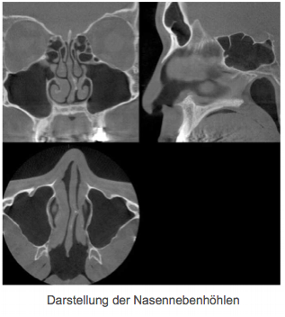

Die neue Technik ermöglicht eine exakte Planung und Realisierung der Behandlung im Kiefer-, Gesicht-, Zahn-, und Nasennebenhöhlenbereich sowie des Ohres. Even- tuelle Operationen, insbesondere Zahnim- plantationen sind dadurch schonender, sicherer und genauer bei reduzierter Eingriffs- dauer durchzuführen.